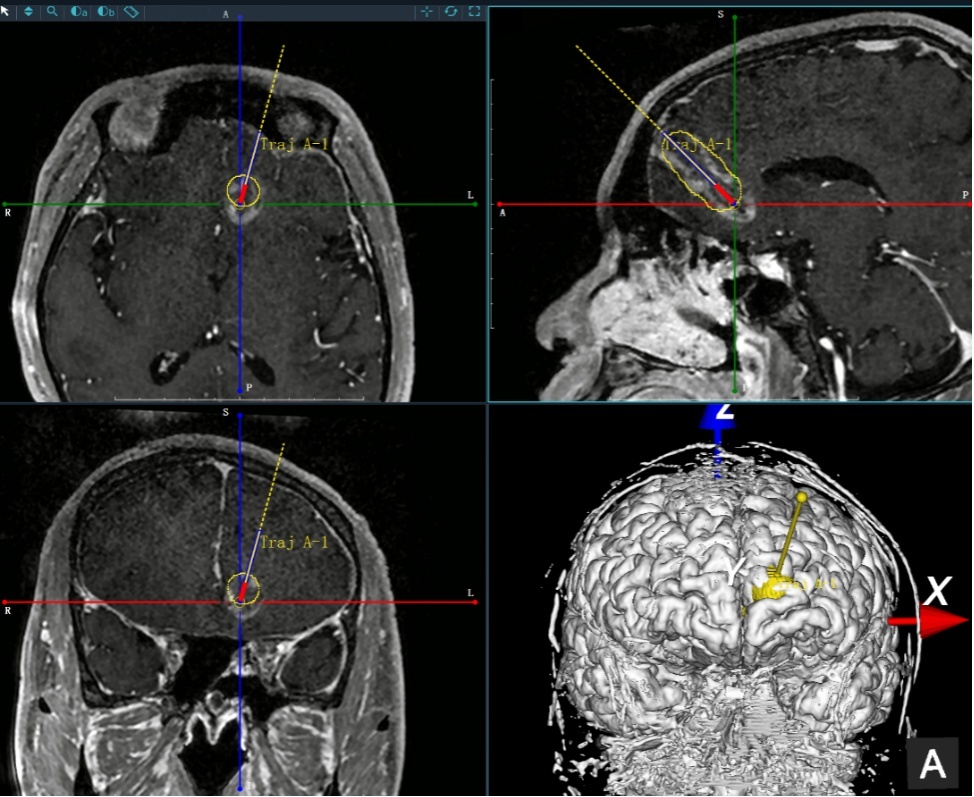

手术如期进行,神经外科科主任王业忠教授运筹帷幄,为手术的顺利进行提供坚强的后盾。在麻醉科、手术室护理团队精诚配合下,主刀胡滨主任医师、助手李伟主治医师紧密合作,严格遵循操作规范,将手术机器人的定位精度提高到亚毫米级,确保可以对手术靶点进行精准定位。

仅4毫米的头皮切口、精准定位的靶点,为患者下一步的热疗提供了坚实基础。患者在手术室植入光纤并复苏后,顺利转运至核磁共振(MR)室。经MR确认光纤位置准确无误后,开始实施热疗。术中通过MR实时监测热疗的效果及范围,与术前预演的范围完美一致。术后顺利拔除光纤,转入神外监护室。